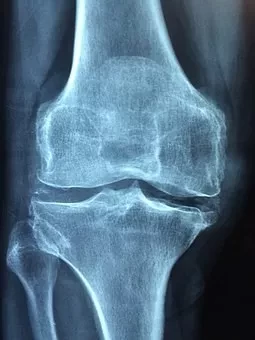

骨性关节炎是最常见的关节炎之一,以中老年居多,是老年人关节致残的主要原因。主要为缓慢进展的关节疼痛、触痛、僵硬、肿大、活动时有骨擦音、关节积液以及活动障碍。

80%的骨性关节炎发生在55~65岁老年人,随年龄增长,发病率增高,66岁以上老年人中几乎人人患有骨性关节炎,只是有人症状重,有人症状轻而未引起。在西方国家中,最常见的关节病为骨性关节炎。我国上海初步调查骨性关节炎的患病率为2%左右。

随着年龄增长,软骨面经过长期磨损,而新陈代谢能力降低,退变加快,软骨破损引起。这种变化一般在20岁以后就发生,30岁后有些人就有一定症状,50岁后60%,60岁以上90%,70岁以后100%软骨有退化。而表现出症状的>20%,求医的仅为5%。滑膜分泌功能减退,对关节软骨的润滑与营养能力降低。